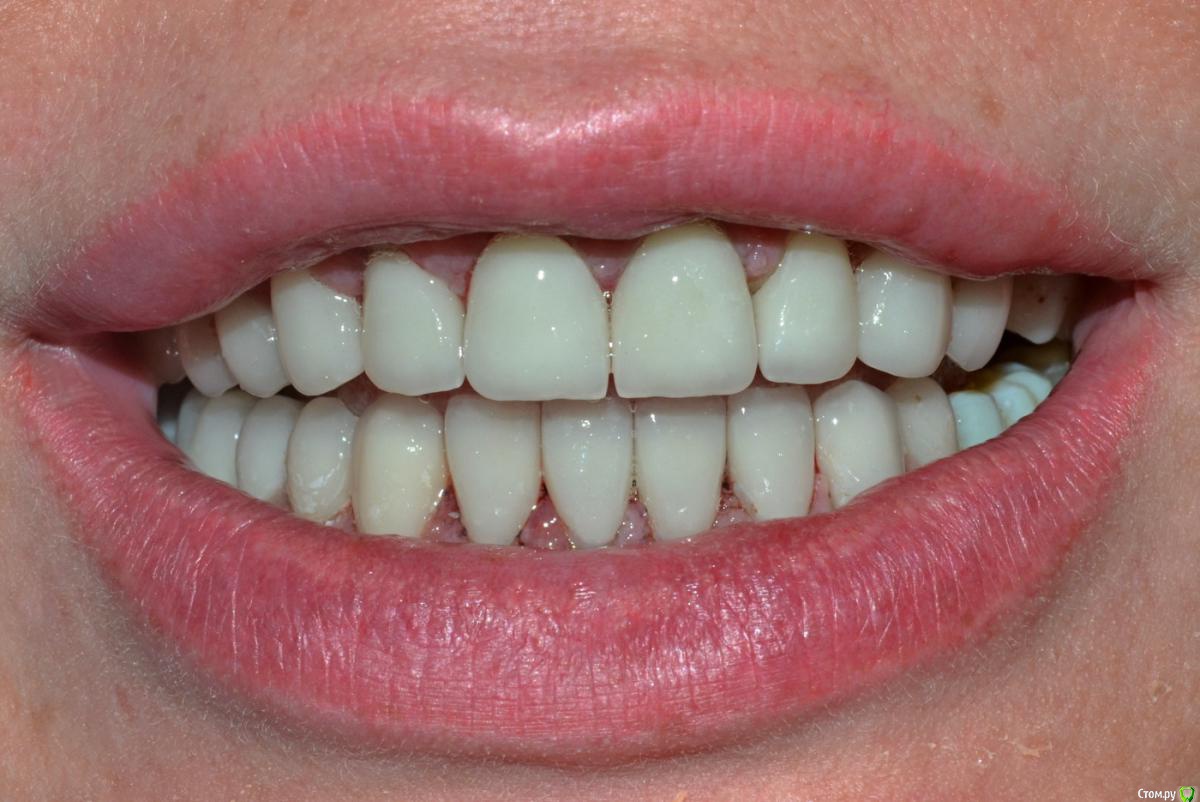

NazranDantist Опубликовано 4 сентября, 2015 Автор Поделиться Опубликовано 4 сентября, 2015 Продолжение кейса. Работа еще не закончена, зуб 25, 35, 36 - аббатменты на подходе, поэтому решили сделать после отпуска пациентки. Фото протокол не соблюдал, курс рубля прыгал, торопился в обменник . Вся работа - имакс на Цереке с редуцированием, фиксация - фронт на чойс, боковые - У-200. Ссылка на комментарий

Freelancer1981 Опубликовано 4 сентября, 2015 Поделиться Опубликовано 4 сентября, 2015 Как цс определяли?Я бы верхние режущий край у верхних зубов(отпрепарированных)загладил,а то разительный контраст с нижними..Фото бы день денька через 3-4.. Ссылка на комментарий

NazranDantist Опубликовано 4 сентября, 2015 Автор Поделиться Опубликовано 4 сентября, 2015 Как цс определяли?Я бы верхние режущий край у верхних зубов(отпрепарированных)загладил,а то разительный контраст с нижними..Фото бы день денька через 3-4..ЦС определял методом джига, высоту "на глаз". Фото сделать нет возможности, пациентка уехала, обещала вернуться Ссылка на комментарий

CHEREDNICHENCO Опубликовано 12 сентября, 2015 Поделиться Опубликовано 12 сентября, 2015 Режет глаз смещение цл, оптг необходимо определенно, хотя бы для оценки состояния тттз и периапикальных тканей в 4 секторе.... Индикатор кариеса используете в работе???.... А зачем в 3 секторе оставили временную конструкцию?! Или это постоянная???..... В десятых- эстетически не вяжется соотношение нижних к верхним... PS: В связи с определенным географическим положением, КНДР находиться в 1 км. 44 м. от места моей работы! и хочу сообщить Вам,- уровень их работ растет от из года, в год! Ссылка на комментарий

NazranDantist Опубликовано 12 сентября, 2015 Автор Поделиться Опубликовано 12 сентября, 2015 Режет глаз смещение цл, оптг необходимо определенно, хотя бы для оценки состояния тттз и периапикальных тканей в 4 секторе.... Индикатор кариеса используете в работе???.... А зачем в 3 секторе оставили временную конструкцию?! Или это постоянная???..... В десятых- эстетически не вяжется соотношение нижних к верхним... PS: В связи с определенным географическим положением, КНДР находиться в 1 км. 44 м. от места моей работы! и хочу сообщить Вам,- уровень их работ растет от из года, в год! А что делать с центральной линией, если она смещена? Кариес индикатор для чего? Про времянки в 3-ем секторе уже написал " Работа еще не закончена, зуб 25, 35, 36 - аббатменты на подходе". Оценка периапекальных тканей проводилась. Ссылка на комментарий

CHEREDNICHENCO Опубликовано 13 сентября, 2015 Поделиться Опубликовано 13 сентября, 2015 Кариеса нет.DSC_0643.JPGСмещение естьПо фото, когда зубные ряды находятся в контакте- смещение есть! Но на первых фото, когда НЧ находиться в состоянии относительного физиологического покоя, смещения нет! ТО делаю вывод, смещение возникает в результате неправильного соотношения жевательных поверхностей зубов. Ссылка на комментарий